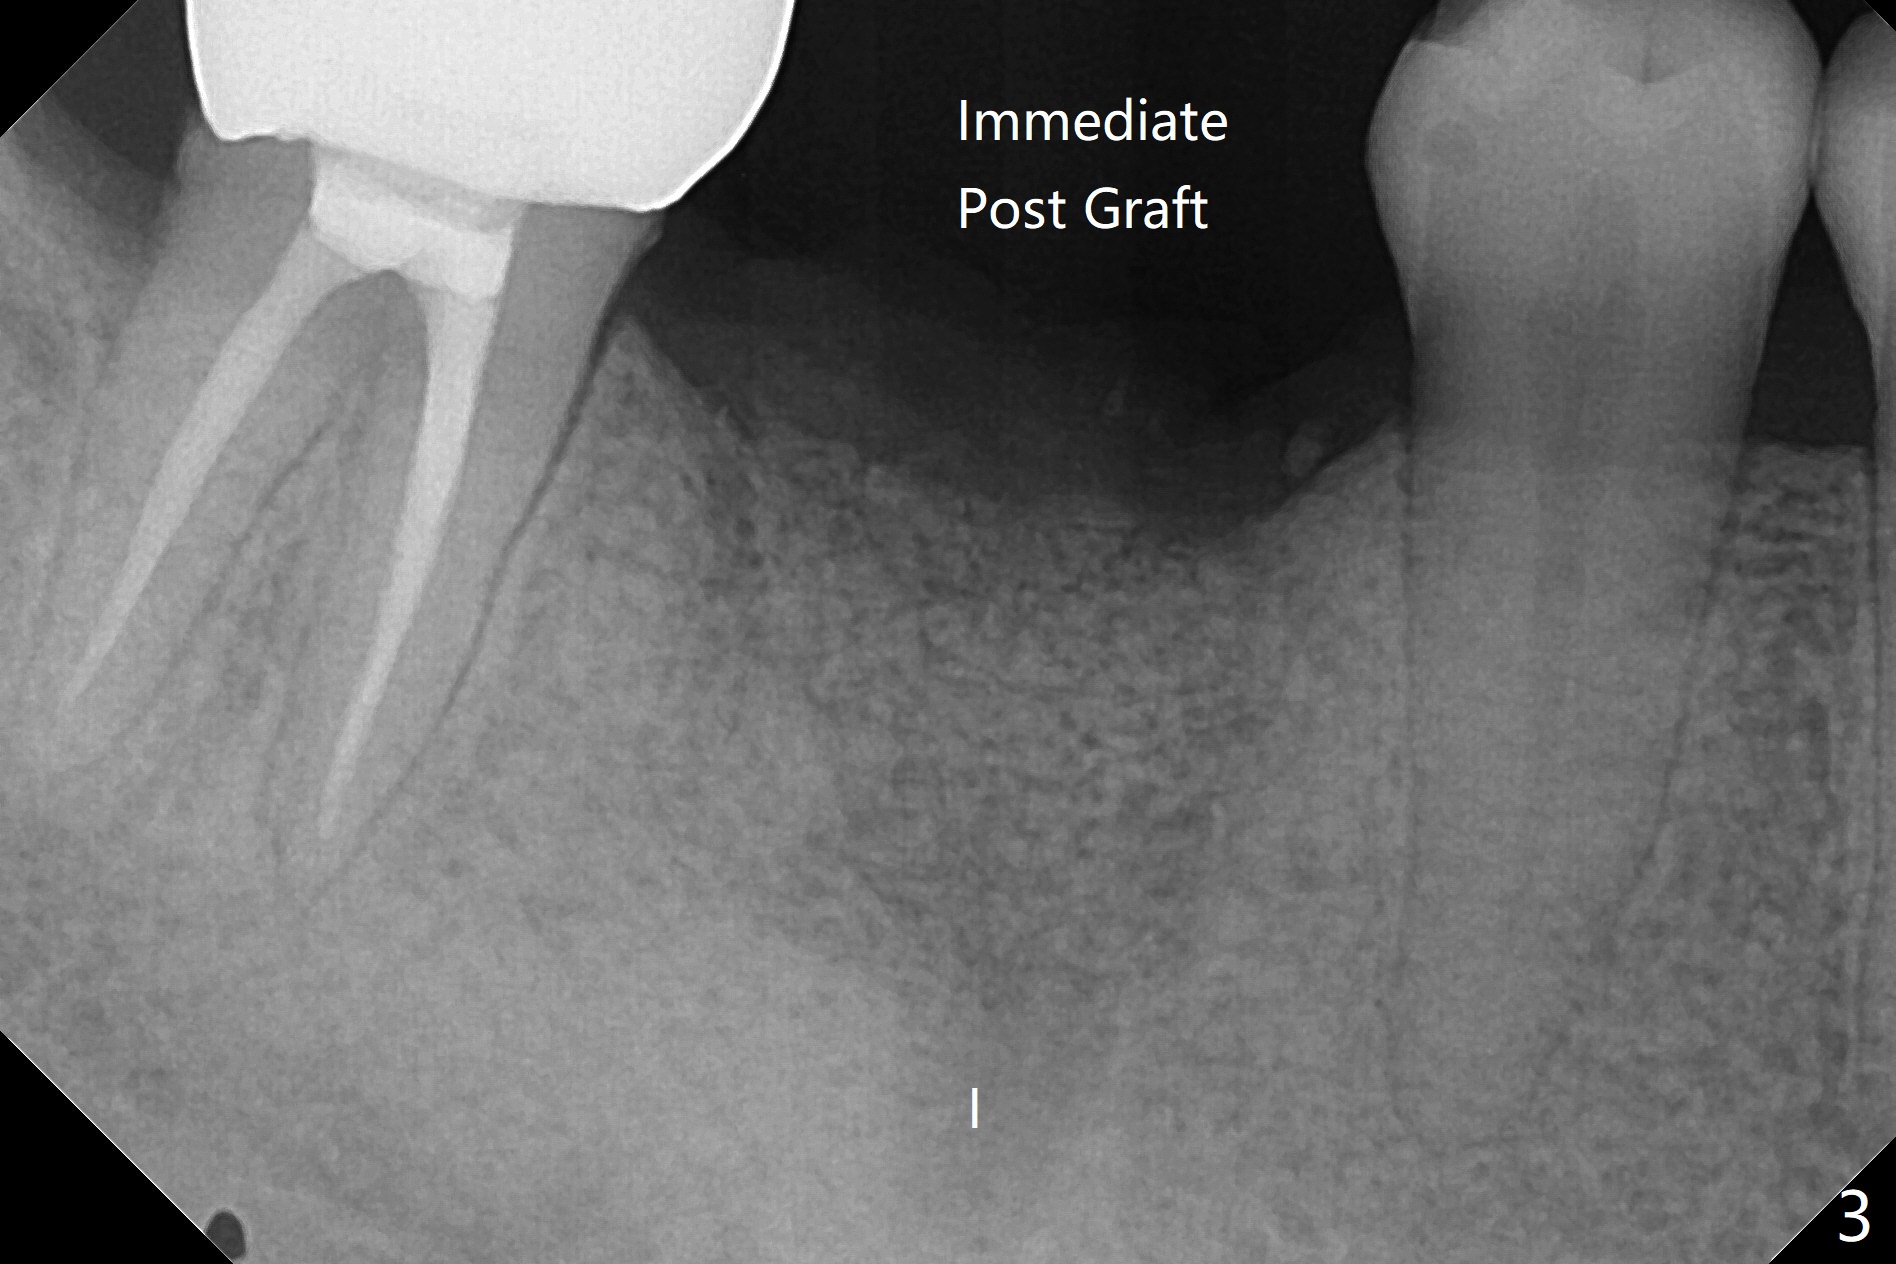

9个月,再次植骨7个月后,颊侧角化龈恢复正常,但是牙槽嵴伤口愈合有些异常(图一:*)。切开后显示螺纹暴露严重,由于整合,必须用环形刀才能取出植体,即刻抽血,植入粘性骨粉,充填植体所在位(图三:I)和颊侧缺损,覆盖PRF膜(x2),松弛切开后,缝合,树脂敷料保护伤口。失败可能原因:植体还偏大(4.5毫米;4毫米两段式五级钛或者3.5毫米一段式),坚硬舌侧骨板迫使植体颊侧移位(最后钻头应该与植体直径一样,适当再种深点)。临时牙冠不应该两周取出,树脂敷料好像更稳妥。